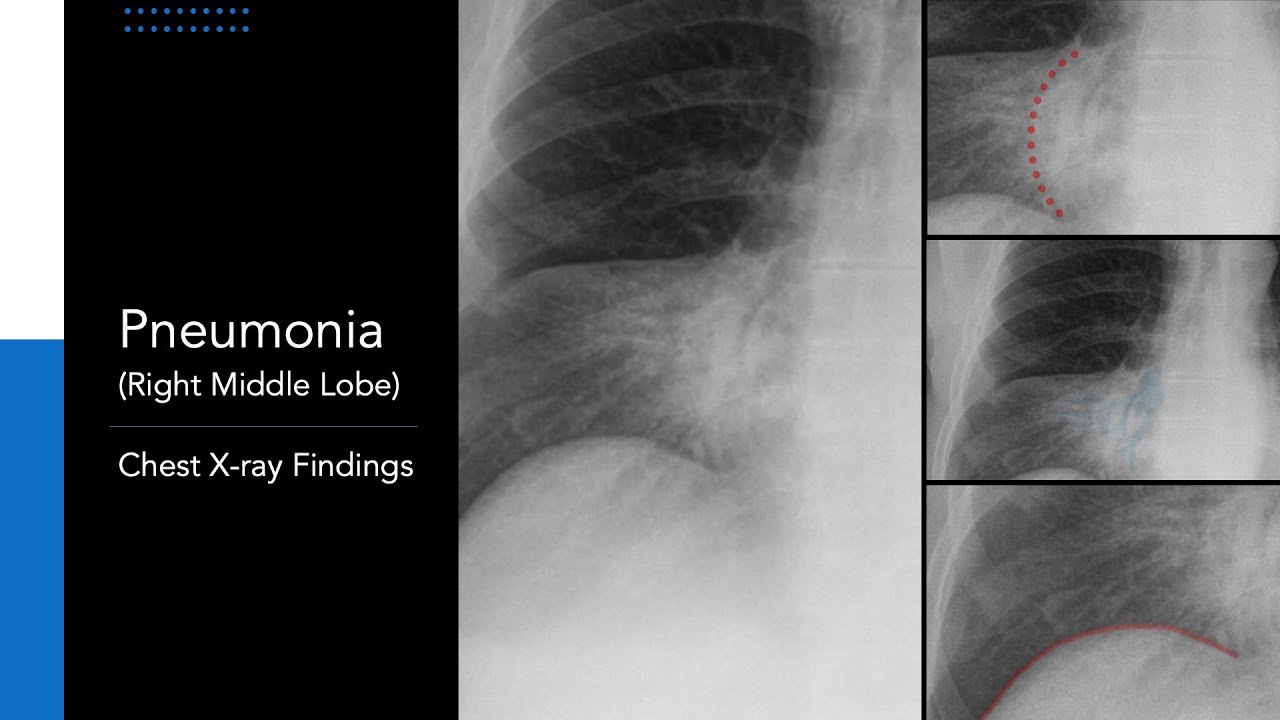

- Pneumonia

CT ground glass for pneumonia

Most often, “ground glass” on CT is manifested in pneumonia, and it can be absolutely any pneumonia: viral, bacterial, with atypical development of the symptom complex, very rare interstitial, and so on. Since the spectrum of causative agents of pneumonia is extremely wide, and it is not always possible to differentiate lung diseases by a single ground-glass effect, the patient is recommended laboratory diagnostics – a blood test or a respiratory secretion for mycoplasmas, pneumococci, coronavirus and other pathogens.

A common symptom of acute pneumonia on CT is the presence of infiltrates (“ground glasses”) of various shapes and lengths. “Ground glasses” are located around the foci or diffusely, as in tuberculosis. However, unlike tuberculosis, their size is usually larger, there is a tendency for the infiltrates to consolidate and form a “cobblestone” pattern. In some cases, the lumen of the bronchi containing gas is visualized. This is called “air bronchography” syndrome. Combined with the ground glass effect, it is also a clear sign of pneumonia.